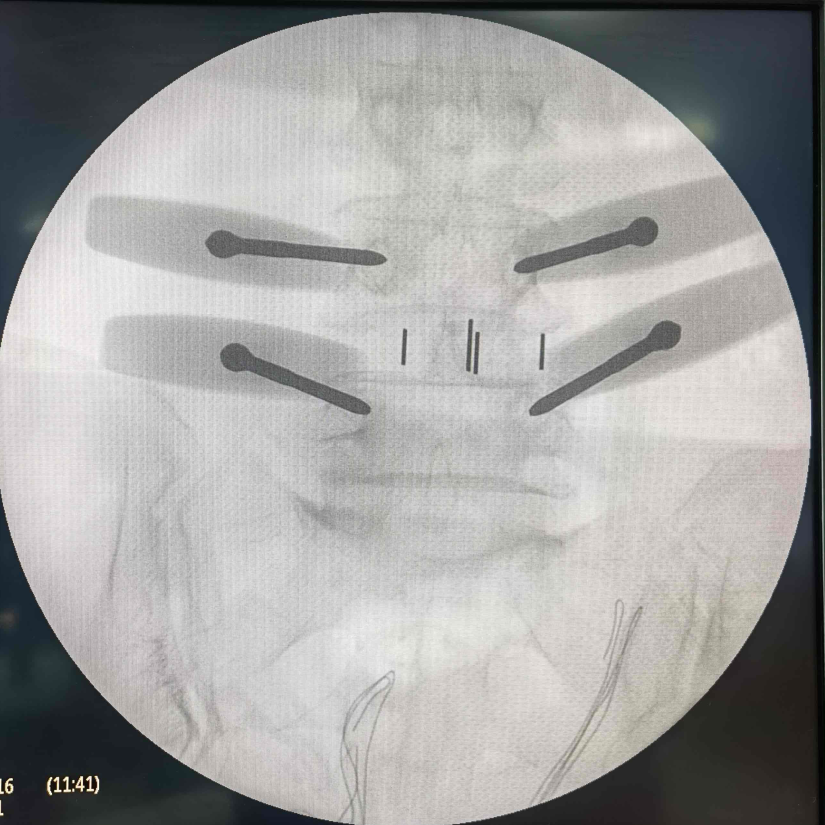

9 月 25 日上午,在浙大四院的手术室里,一场 「双通道内镜下腰椎大融合器融合术」正有条不紊地推进。手术台旁,除了主刀的医护团队,五位哥伦比亚专家屏息凝神,生怕错过任何一个操作细节。

「这位患者因腰椎不稳、伴椎管狭窄,长期受腰痛、腿痛困扰。今天我们用的是创新改良的技术,在没有辅助通道的情况下,直接通过操作通道将大融合器植入……」 手术间隙,浙大四院骨科主任胡庆丰一边精准操作器械,一边用清晰的讲解,把手术关键要点传递给身旁的 「学生们」。

相较于传统开放手术或单一通道内镜技术,「双通道内镜下腰椎融合术」是脊柱微创领域的一项重要创新。

这项技术通过两个微小的切口,分别置入内镜观察镜和手术器械,相当于医生有了「一双灵巧的手」,能在高清放大的视野下精准处理病灶、植入融合器,具有创伤更小、出血更少、神经损伤风险低、术后恢复快的显著优势。

而浙大四院在此基础上进一步优化的「无辅助通道大融合器置入」技术,更是简化了步骤,提升了手术效率,使患者获益更大。